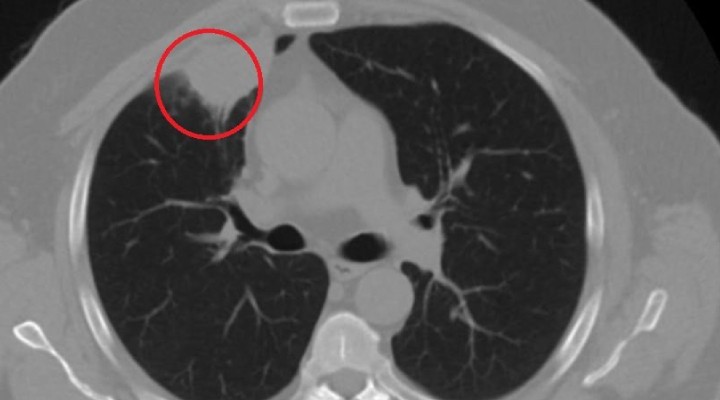

– Hastamız, çalıştığı başka bir kentte göğsünden darbe alıyor ve ağrıları geçmeyince bir üniversite hastanesine başvuruyor. Burada hastaya bir akciğer grafisi çekiliyor. Sağ akciğerinde bir kitleye rastlanıyor. Daha sonra hastaya, bir akciğer tomografisi çekiliyor ve göğüs cerrahisi için önemli büyüklükte olan 4 santimetre çapında, akciğer kanserine benzer özellikte radyolojik bulgular olan bir kitle tespit ediliyor. Daha sonra hastaya yapılan ileri tetkiklerde akciğer kanseri teşhisi konuluyor. Hastaya bir cerrahi planlanıyor.

– Hasta Kahramanmaraşlı olduğu için kendi memleketine gelmeyi tercih ediyor. Bize başvurdu ve göğüs ağrısı şikayeti vardı. Öksürük, nefes darlığı, balgam çıkarma, ateş gibi şikayetleri yoktu. Hastayı biz de değerlendirdik ve ameliyat olmasına karar verdik. Çünkü akciğer kanserine çok benzer radyolojik bulguları vardı. Sağlık Bakanlığımızın kuralları gereği her hastayı ameliyat öncesi PCR testi yapılır. Biz de ameliyat gecesi hastadan PCR testi aldık ve testi pozitif geldi. Ameliyatımızı 14 gün erteledik ve hastamıza corona tedavisi uygulandı.

– 14’üncü gün tekrar bize başvurdu ve yapılan PCR testi negatif çıktı. Yeni bir tomografi çektik ve tümörün tamamen ortadan kalktığını gördük. Şimdi sonuç bilgilerinden başlangıca gittiğimizde, bu bir akciğer kanseri olsaydı, ortadan kalkması mümkün değildi. Başka bir patolojiye bağlı durum olsaydı, yine verdiğimiz tedaviyle ortadan kalkmasını çok beklemeyiz. Antiviral tedavisi verdik ve hastanın radyolojik bulguları neredeyse tamamen normale döndü. Hastaya bunu izah ettik, ‘Dünya literatüründe hiç görülmeyen bir radyolojik bulgu’ diyerek. Bu gördüğümüz manzara artık hastanın akciğer grafisinde yok, akciğer kanseri değil.

Genel olarak dünya literatürüne baktığımızda virüsün akciğer bulguları, radyolojik bulguları infiltrasyon, buzlu cam dansitesi gibi bilinen bulgular. Ama bizim hastamızda akciğer tümörünü taklit eden bir kitle vardı. Ve biz bunu dünya literatüründe hiç görmemiştik. Bununla ilgili geniş çaplı bir araştırma yaptım. Hem kendi deneyimlerimden hem kendi hastanemizde yatan hastalardan yola çıkarak birçok hastanın radyolojik bulgularına baktık. Dünya literatürlerini karıştırdım, diğer arkadaşlarıma danıştım, benzeri bulguya rastlamadım.